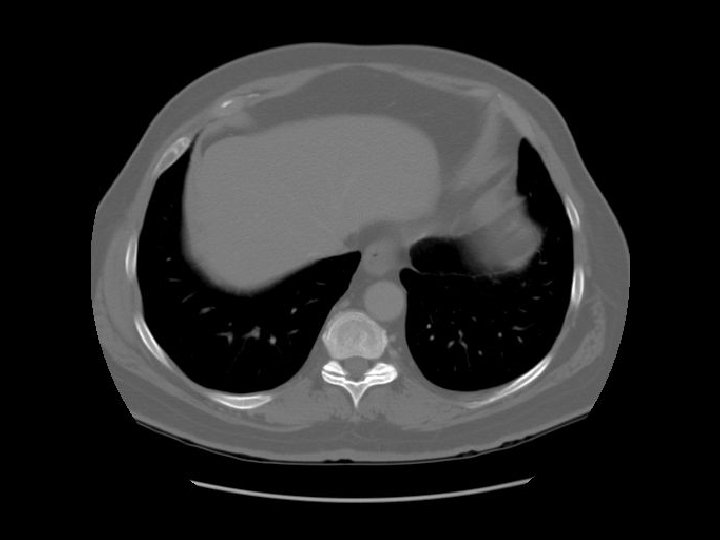

Stomach Liver Spleen

Lt lobe Rt lobe